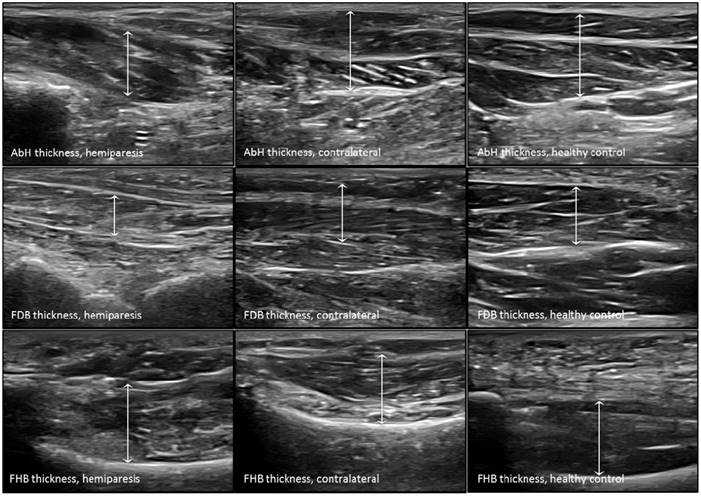

The probe was located according to prior research studies about RUSI measures of the intrinsic plantar muscles and fascia [8-10]. First, the PF was assessed in a longitudinal line from the medial calcaneal tubercle to the 2nd toe. The PF was divided into 3 points of evaluation: 1) the calcaneus insertion (PF-1), b) the navicular tubercle (PF-2), and 3) the 2nd metatarsal head (PF-3). Second, the CSA (perpendicular to the muscle fibers) and the thickness (longitudinal to the muscle fibers) were assessed in the thickest part of the muscles (AbH, FDB and FHB) coinciding with 3 different scanning lines. Indeed, the AbH scanning line was located from the medial calcaneus bone tuberosity to the navicular bone tuberosity. After, the FDB scanning line was placed between the medial calcaneus tuberosity bone tubercle to the 3rd toe. Lastly, the FHB scanning line was longitudinally placed along the 1st metatarsal shaft (8,9). Regarding the RUSI measurements of the PF thickness (Figure 1), intrinsic plantar muscles CSA (Figure 2) and thickness (Figure 3) obtained in the hemiparesis, contralateral and healthy matched control feet, subjects who presented difficulties to evaluate the muscles and PF limits (i.e. structures larger than the probe footprint or ultrasound images with poor visually perimeters) were excluded [10].

Ultrasound imaging measurements of the intrinsic plantar muscles thickness. Abbreviations: AbH, abductor hallucis; FDB, flexor digitorum brevis; FHB, flexor hallucis brevis.